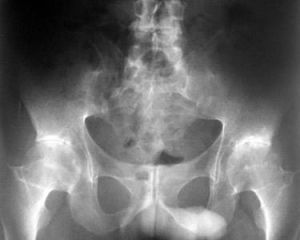

無論是X線、CT或MRI檢查均顯示典型的退行性變徵象,並依據其退變所處的階段不同而呈現出相應的改變。1.X線檢查(1)椎節不穩屬病變早期,或同一病例病變較輕的椎節。在動力性攝片時(側位)可顯示出鬆動與不穩征,一般是上一椎體的下緣在下一椎體的上緣前後滑動,並出現梯形變。側向鬆動與不穩則較少見。(2)椎間隙狹窄由於椎間盤退變,早期即可顯示患節間隙變窄,並隨著脫水加劇,以及軟骨面受累而使椎間隙的垂直高度明顯降低,甚至僅為正常椎間隙的1/3或1/4。(3)椎節骨質增生在椎體邊緣可顯示出大小不一、形態各異的骨質增生。(4)小關節骨質增生除椎體邊緣骨刺外,小關節骨質增生亦較多見,因該處骨組織重疊密集而難以判定。因此,當懷疑該處有骨質增生,且伴有根性受壓症狀需定位選擇術式時,則需行CT檢查。(5)其他改變除骨贅外,X線片上尚可發現鄰近椎節鬆動與不穩征,此乃由於相鄰椎節活動量增加之故。並應注意第5腰椎椎弓根有無退變性斷裂,其可伴發。同時,酌情測量椎管和(或)根管的矢狀徑以判定有無繼發性椎管狹窄症。 2.CT檢查對下腰椎傷病的診斷意義較大,其陽性發現率明顯高於普通X線檢查,尤其是在對椎管及側隱窩形態與大小的判定上具有較高的臨床價值。三維椎管形態重建更有助於對椎管及根管狀態的判定,而且可作為手術選擇的依據之一。 3.MRI檢查此項檢查主要用於對硬膜囊狀態的判定,因此凡具有脊髓、脊神經根症狀者,應常規予以檢查。